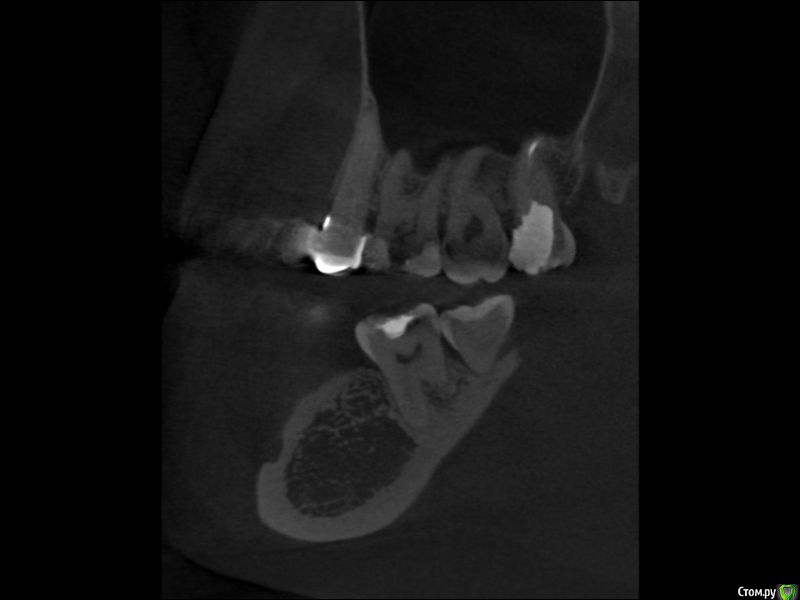

rex11 Опубликовано 11 января, 2017 Поделиться Опубликовано 11 января, 2017 Здравствуйте, уважаемые врачи.Скажите, пожалуйста, что вы видите на этом срезе КТ?На мой взгляд, здесь в зубе 2\7 средний кариес, а в зубе 3\7 маленький кариес под пломбой. Права ли я и насколько срочное лечение требуется в этих случаях? Заранее больое спасибо! Ссылка на комментарий

IvanK Опубликовано 12 января, 2017 Поделиться Опубликовано 12 января, 2017 По Вашим срезам кт понять что-то сложно.. Я бы советовал диагностику оставить Врачу) Ссылка на комментарий

rex11 Опубликовано 12 января, 2017 Автор Поделиться Опубликовано 12 января, 2017 По Вашим срезам кт понять что-то сложно.. Я бы советовал диагностику оставить Врачу) А рентгентовский снимок для Вас также неинформативен? Ссылка на комментарий